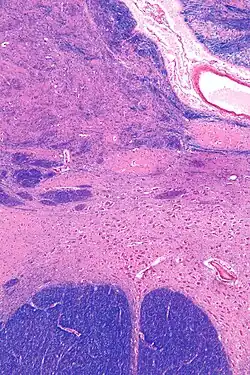

![]() Intermediate magnification micrograph of the nucleus basalis. LFB-HE stain. | |

The nucleus basalis in humans is a somewhat diffuse collection of large cholinergic neurons in the basal forebrain.[2] The main body of the nucleus basalis lies inferior to the anterior commissure and the globus pallidus, and lateral to the anterior hypothalamus in an area known as the substantia innominata.[1] Rostrally, the nucleus basalis is continuous with the cholinergic neurons of the nucleus of the diagonal band of Broca.[1] The nucleus basalis is thought to consist of several subdivisions based on the location of the cells and their projections to other brain regions.[2] Occasional neurons belonging to the nucleus basalis can be found in nearby locations such as the internal laminae of the globus pallidus and the genu of the internal capsule.[1]